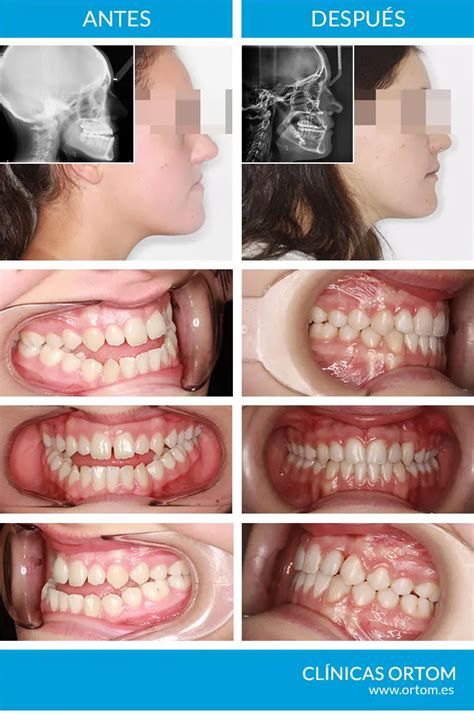

Un claro ejemplo de la colaboración es el tratamiento de ortodoncia y cirugía ortognática. Desde el inicio, el ortodoncista y el cirujano maxilofacial diseñan un plan conjunto. Primero, el ortodoncista alinea los dientes. Luego, el cirujano realiza la cirugía para corregir la posición de los huesos. Finalmente, el ortodoncista realiza los ajustes finales.